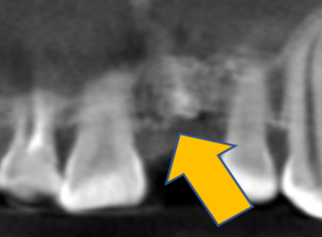

| 1127 #15 右上第二小臼齒 |

![]() |